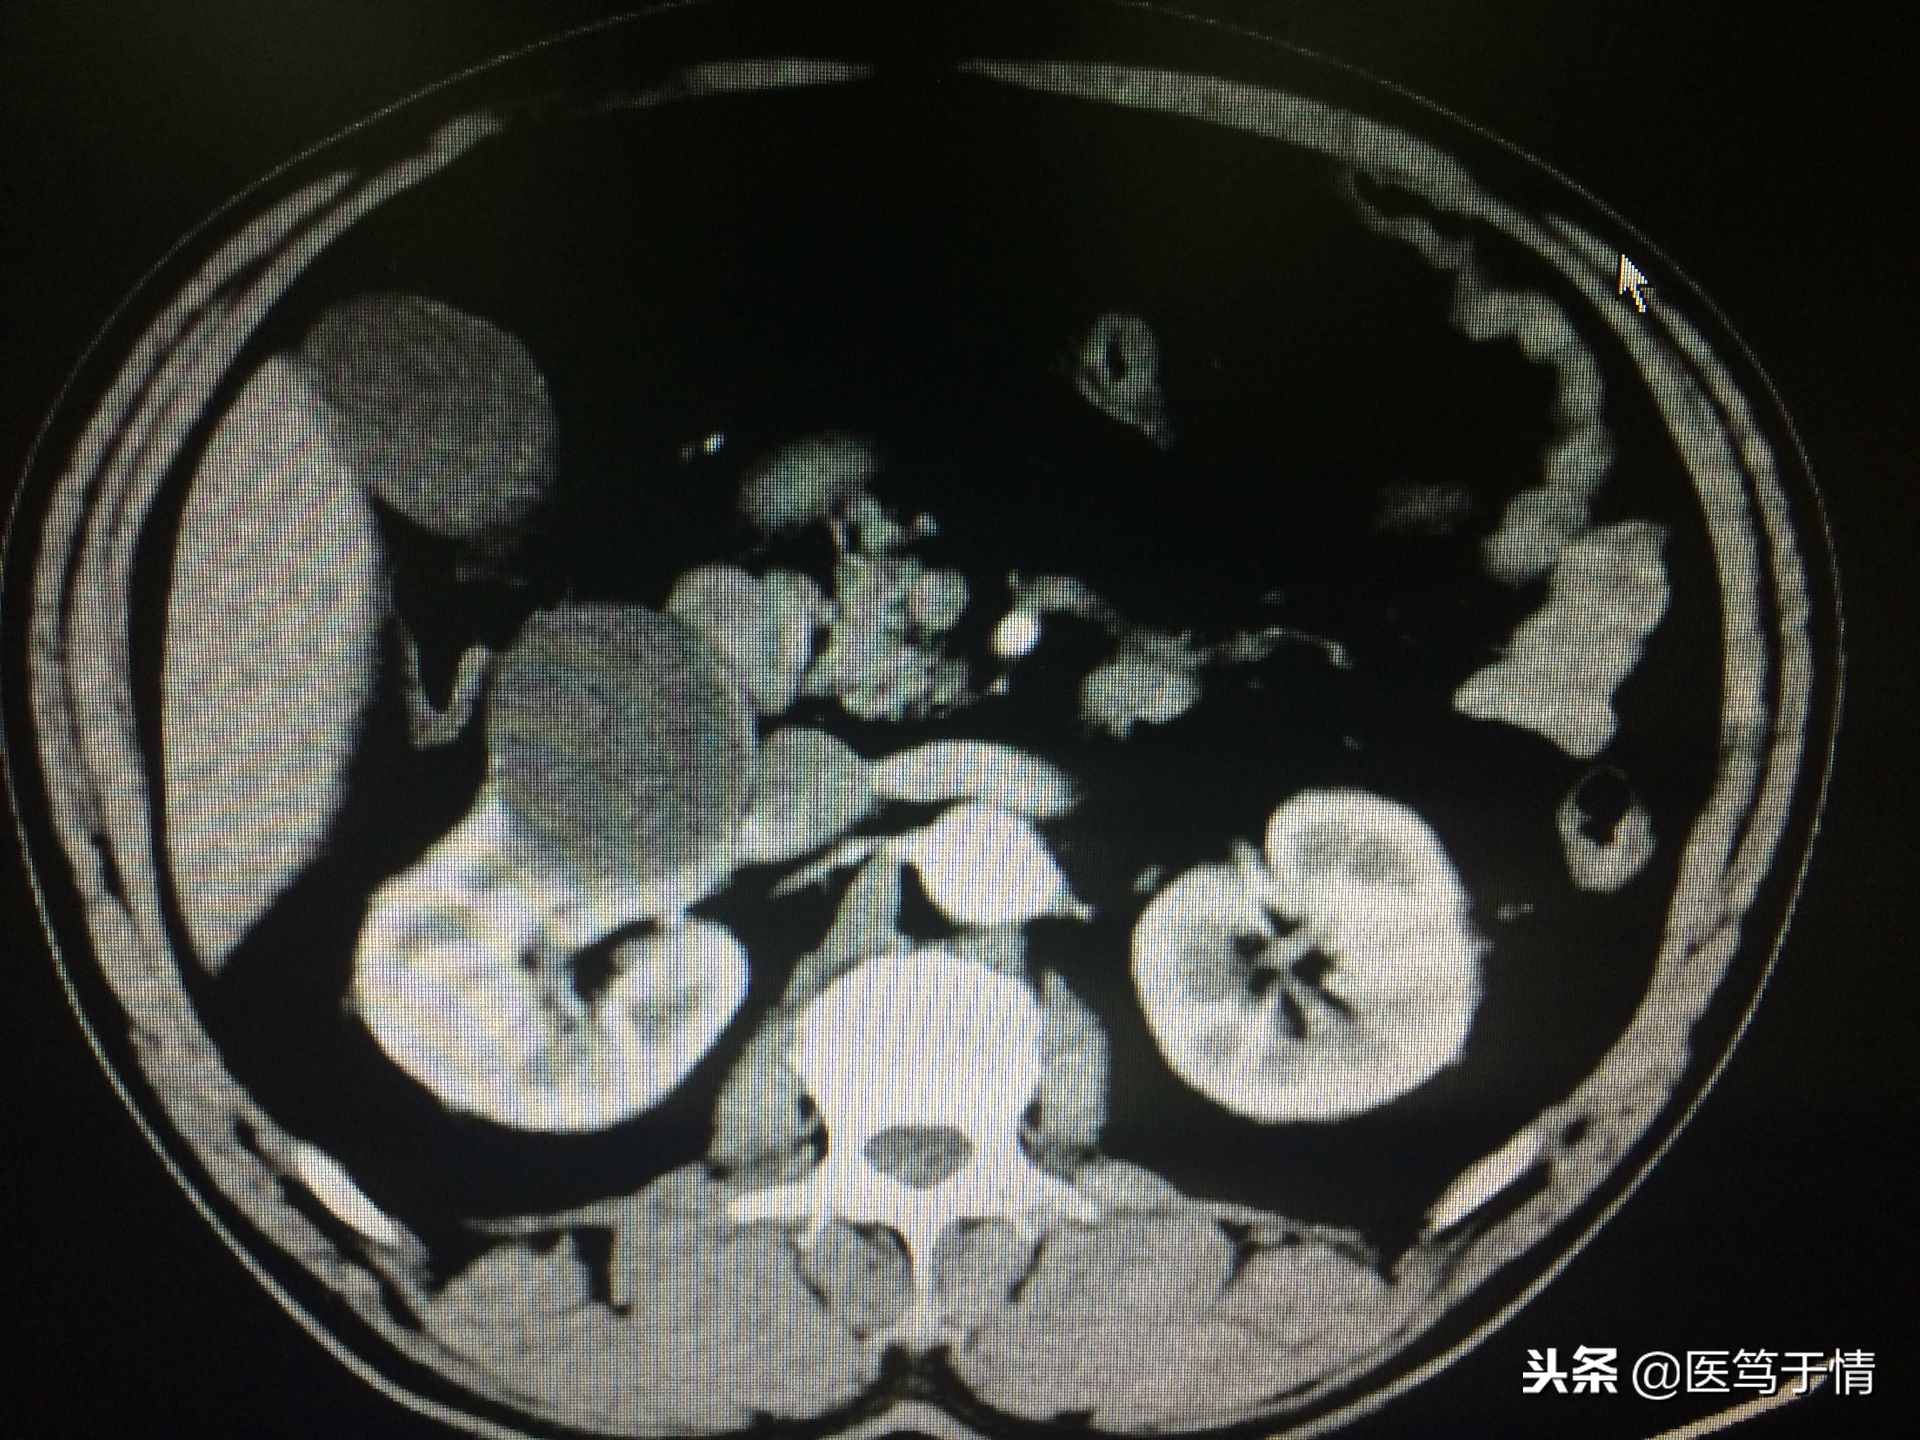

图一:男,57,查体发现右肾囊肿,影像学提示囊壁略增厚强化,腹腔镜肾囊肿去顶后病理报恶性,2016年3月行肾切除;